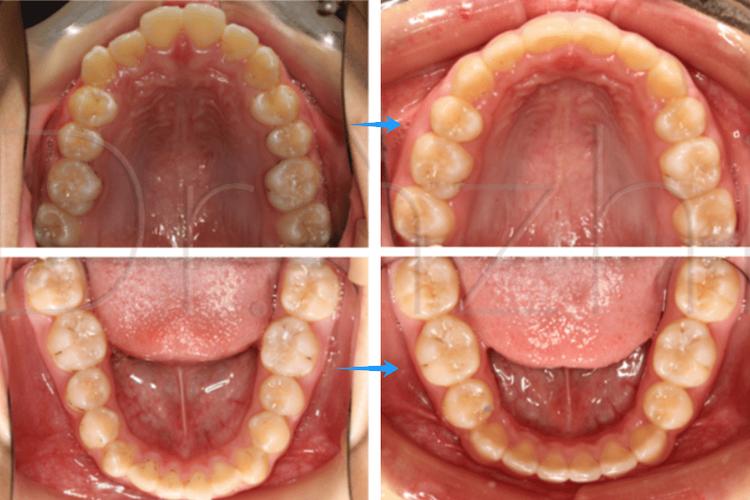

矫正拔牙并非“随便拔”,而是需通过专业检查(如X光片、模型分析、数字化口扫等)后,选择对功能、美观影响最小的牙齿,对于“拔两颗牙”的情况,最常见的是拔除上下颌第一前磨牙(位于尖牙和磨牙之间,编号为4或5),具体原因如下:

前磨牙的“位置优势”

前磨牙位于牙弓中段,拔除后既能提供足够空间,又不会影响前牙的美观和后牙的咀嚼功能,相比门牙(影响笑容)和磨牙(重要咀嚼牙),前磨牙的“牺牲成本”最低。

对称性拔除,保持牙弓稳定

通常采用“上下颌对称拔除”原则(如上颌左右各1颗第一前磨牙,下颌左右各1颗第一前磨牙,共4颗;或单侧上下颌各1颗,共2颗),这样可避免牙弓不对称导致的咬合偏移,保持面部肌肉平衡。

拔除前磨牙后,牙齿可通过“倾斜移动”“整体移动”等方式调整位置,医生可通过正畸装置(如托槽、弓丝)精确控制牙齿移动方向,最终实现排列整齐、咬合稳定。